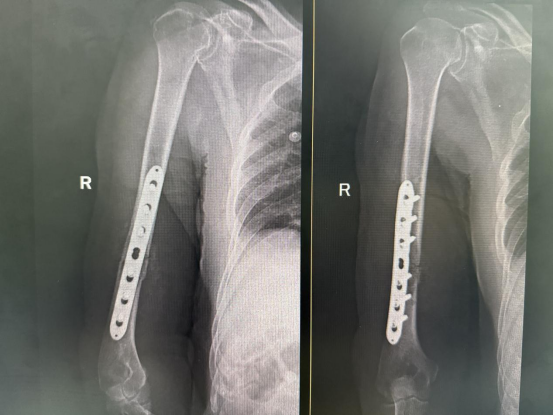

术后DR复片